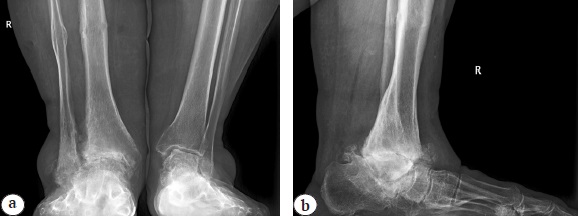

A 64-year-old woman with complaints of pain and deformity of the posterior part of the right foot, lameness applied to the orthopedics clinic of the NIITO named after Ya.L. Tsivyan. In 2008, for a Maisonneuve fracture, the patient received conservative treatment with poor results. In this regard, in 2009, she underwent an attempt of arthrodesis of the posterior part of the foot in an external fixation device, which was unsuccessful. After 5 years, there was a sharp deterioration in the condition, increased swelling, pain, rapid progression of foot deformity (Fig. 1).

Fig. 1. Lower extremities before surgery

Radiological examination methods (radiography, MRI, MSCT of the ankle joint) showed undoubted signs of posttraumatic AVN of the talus and its complications in the form of collapse of the talus, multiple cysts of the tibia, talus, calcaneus, etc. (Fig. 2, 3, 4).

Fig. 2. X-rays of the ankle joints: a — AP X-ray: posttraumatic degenerative distal tibial diastasis, suspicion of gross valgus deformity of the ankle area, 3 stage of posttraumatic deforming osteoarthritis of the ankle joint; b — X-ray in lateral projection: collapse of the talus body, arch of the foot, 3 stage of deforming osteoarthritis of the ankle, talonavicular joint, ankylosis of the subtalar joint